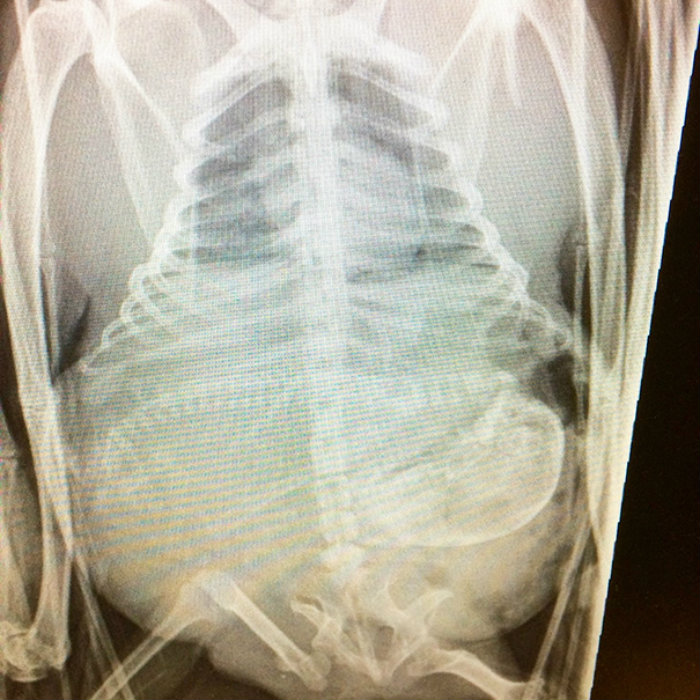

1. Bats are coming.

This bat is ready to have some babies!